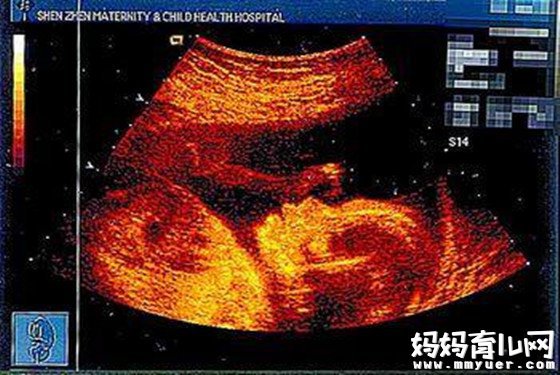

怀孕八个月男胎儿图

怀孕32周,他的身体和四肢还在继续长大,最终要长得与头部比例相称。胎儿现在的体重为2000克左右,全身的皮下脂肪更加丰富,皱纹减少,看起来更像一个婴儿了。现在胎儿动得次数比原来少了,动作也减弱了,再也不会像原来那样你的肚子里翻筋斗了。